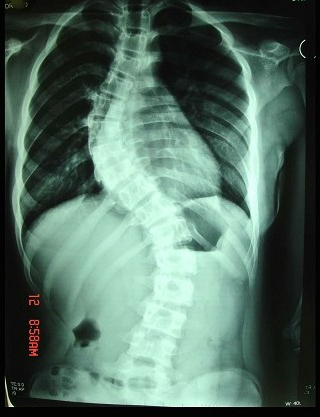

脊柱侧凸的临床表现错误的是()

A:多发生在儿童和青少年

B:多发生在女性

C:18~20岁后侧凸进入稳定期

D:侧凸严重时,可引起心悸、气急

E:10岁以后畸形发展快

脊柱侧弯矫形后腰前凸消失的原因为()

A:腰段特别是腰骶段撑开固定

B:原有胸腰段后凸畸形

C:胸椎后凸畸形僵硬

D:髋关节屈曲挛缩

E:以上都是